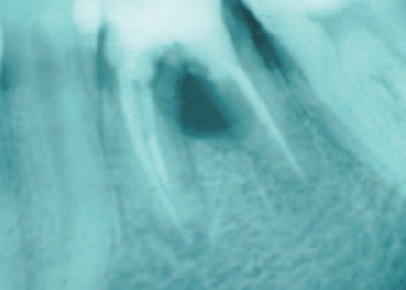

На рис. 2 представлена прицельная внутриротовая рентгенограмма зуба 37 с обширным разрежением костной ткани в области бифуркации. При проведении удаления зуба 37 необходима профилактика постэкстракционного альвеолита, причиной возникновения которого может стать микрофлора гнойного отделяемого из очага деструкции костной ткани. Учитывая инфекционную природу процесса, в подобных случаях необходимо проводить удаление зубов под прикрытием противомикробных препаратов, а пациенту строго соблюдать рекомендации, особенно связанные с отказом от употребления алкогольных напитков и курения в постэкстракционном периоде.

Рис. 2. После удаления зуба 37 необходимо проведение профилактики постэкстракционного альвеолита, связанного с микрофлорой гнойного экссудата.